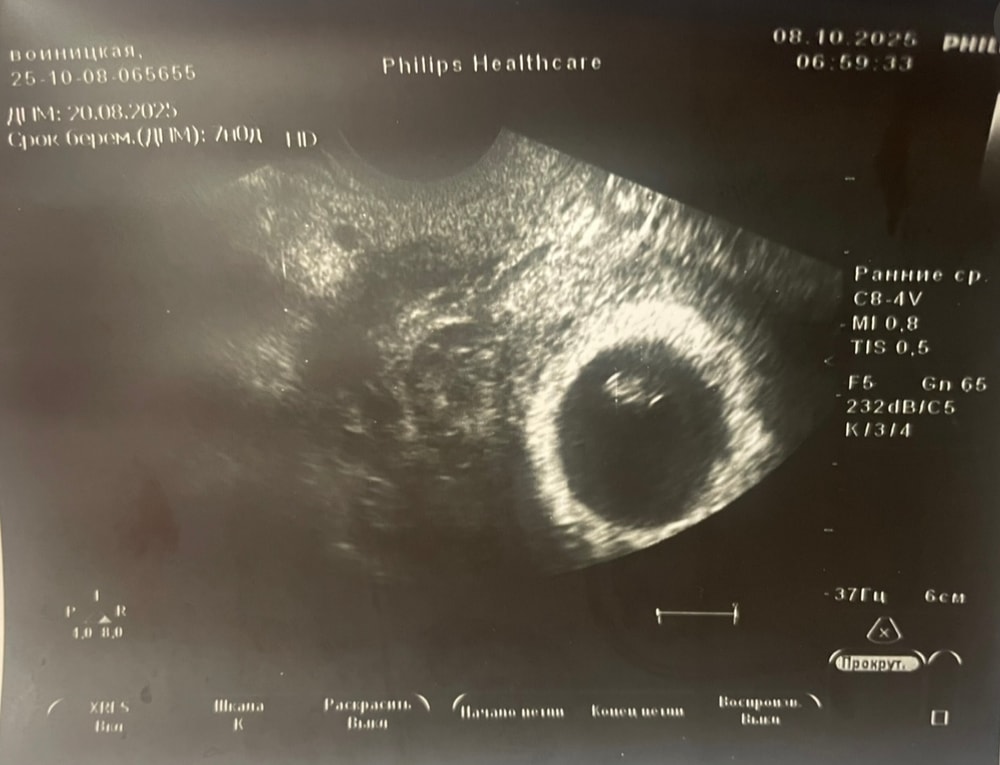

Сегодня на УЗИ подтвердили сердцебиение. Показали малявку, КТР 6,6 мм, ну какая же кроха🥹 Я начинаю понемногу въезжать в понимание, что снова буду с малышом, но еще пока очень страшно.

Ну и первая фотка, на память)